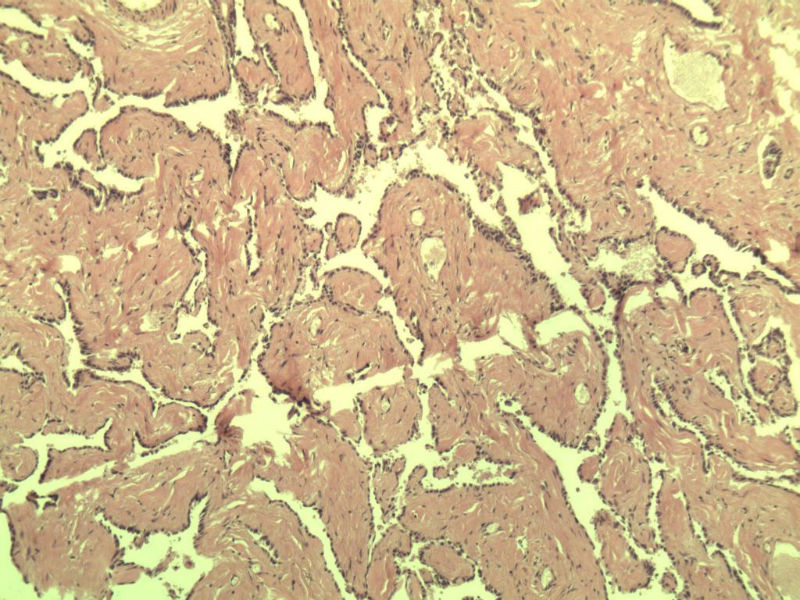

男 27岁 腹腔隐睾 5*3*2 cm, 切面灰红灰黄、实性、质中,请各位老师看看,是精原细胞瘤吗?感觉不像.腹腔隐睾图1

典型的精原细胞瘤,隐睾易恶变